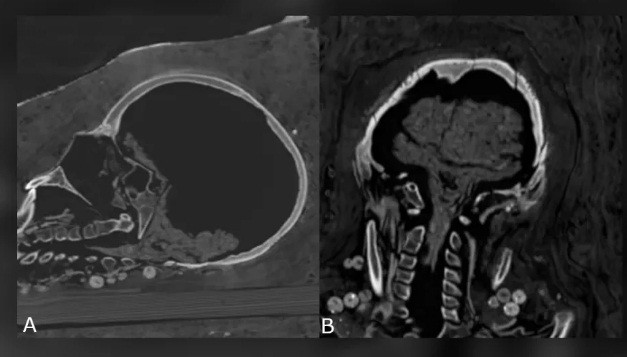

Hai người này qua đời khi còn khá trẻ. Trong khi người đàn ông cao 1,64m qua đời khi khoảng 25 - 30 tuổi thì người phụ nữ có chiều cao 1,56m chết khi 30 - 40 tuổi.

Tuy nhiên, hiện các chuyên gia chưa thể tìm ra nguyên nhân tử vong của họ. Các chuyên gia mới phát hiện người phụ nữ gặp một số vấn đế về sức khỏe, trong đó có bệnh viêm khớp.